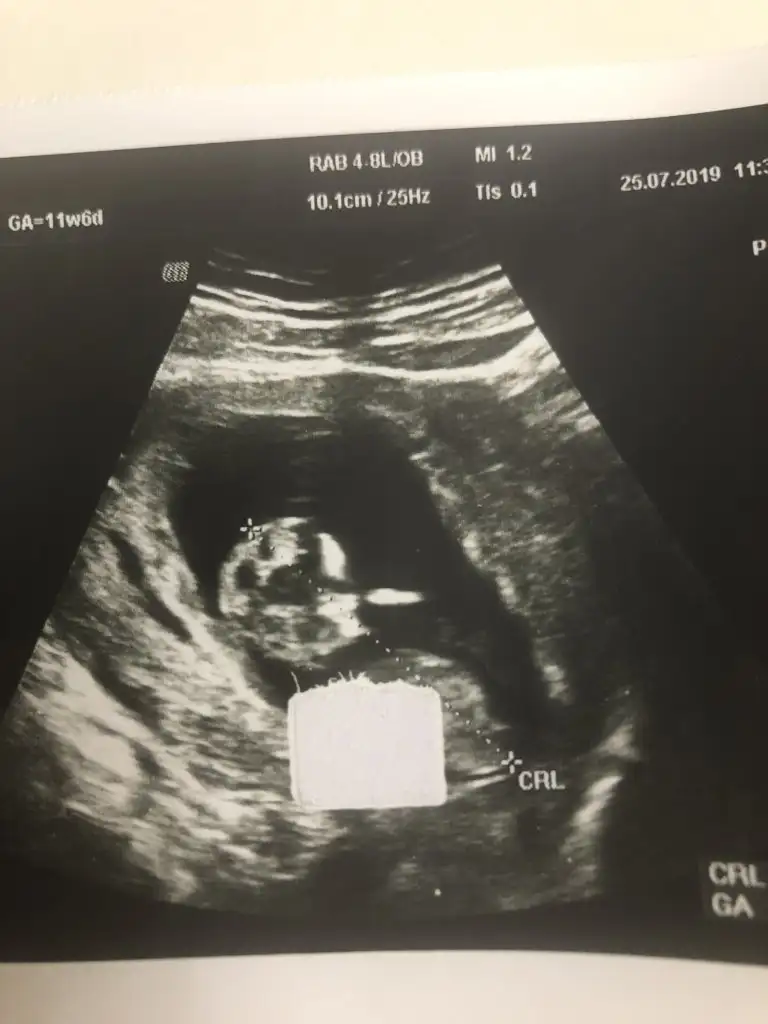

Erkek gibi kafa sekline yorumluyorum nub artık olmaz 13 hafta sanırımArkadaşlar daha önce yorum yapmıştınız ama doktor kesin bişey söylemiyor bunada bakabilir misiniz

Evet teşekkür ederimmmErkek gibi kafa sekline yorumluyorum nub artık olmaz 13 hafta sanırım

KizzArkadaşlar daire içine aldığım yermi nub oluyor bide yorumlayabilirmisiz lütfen

Tam dik degil ama ben tahminimi Erkek gibi yorumluyorum